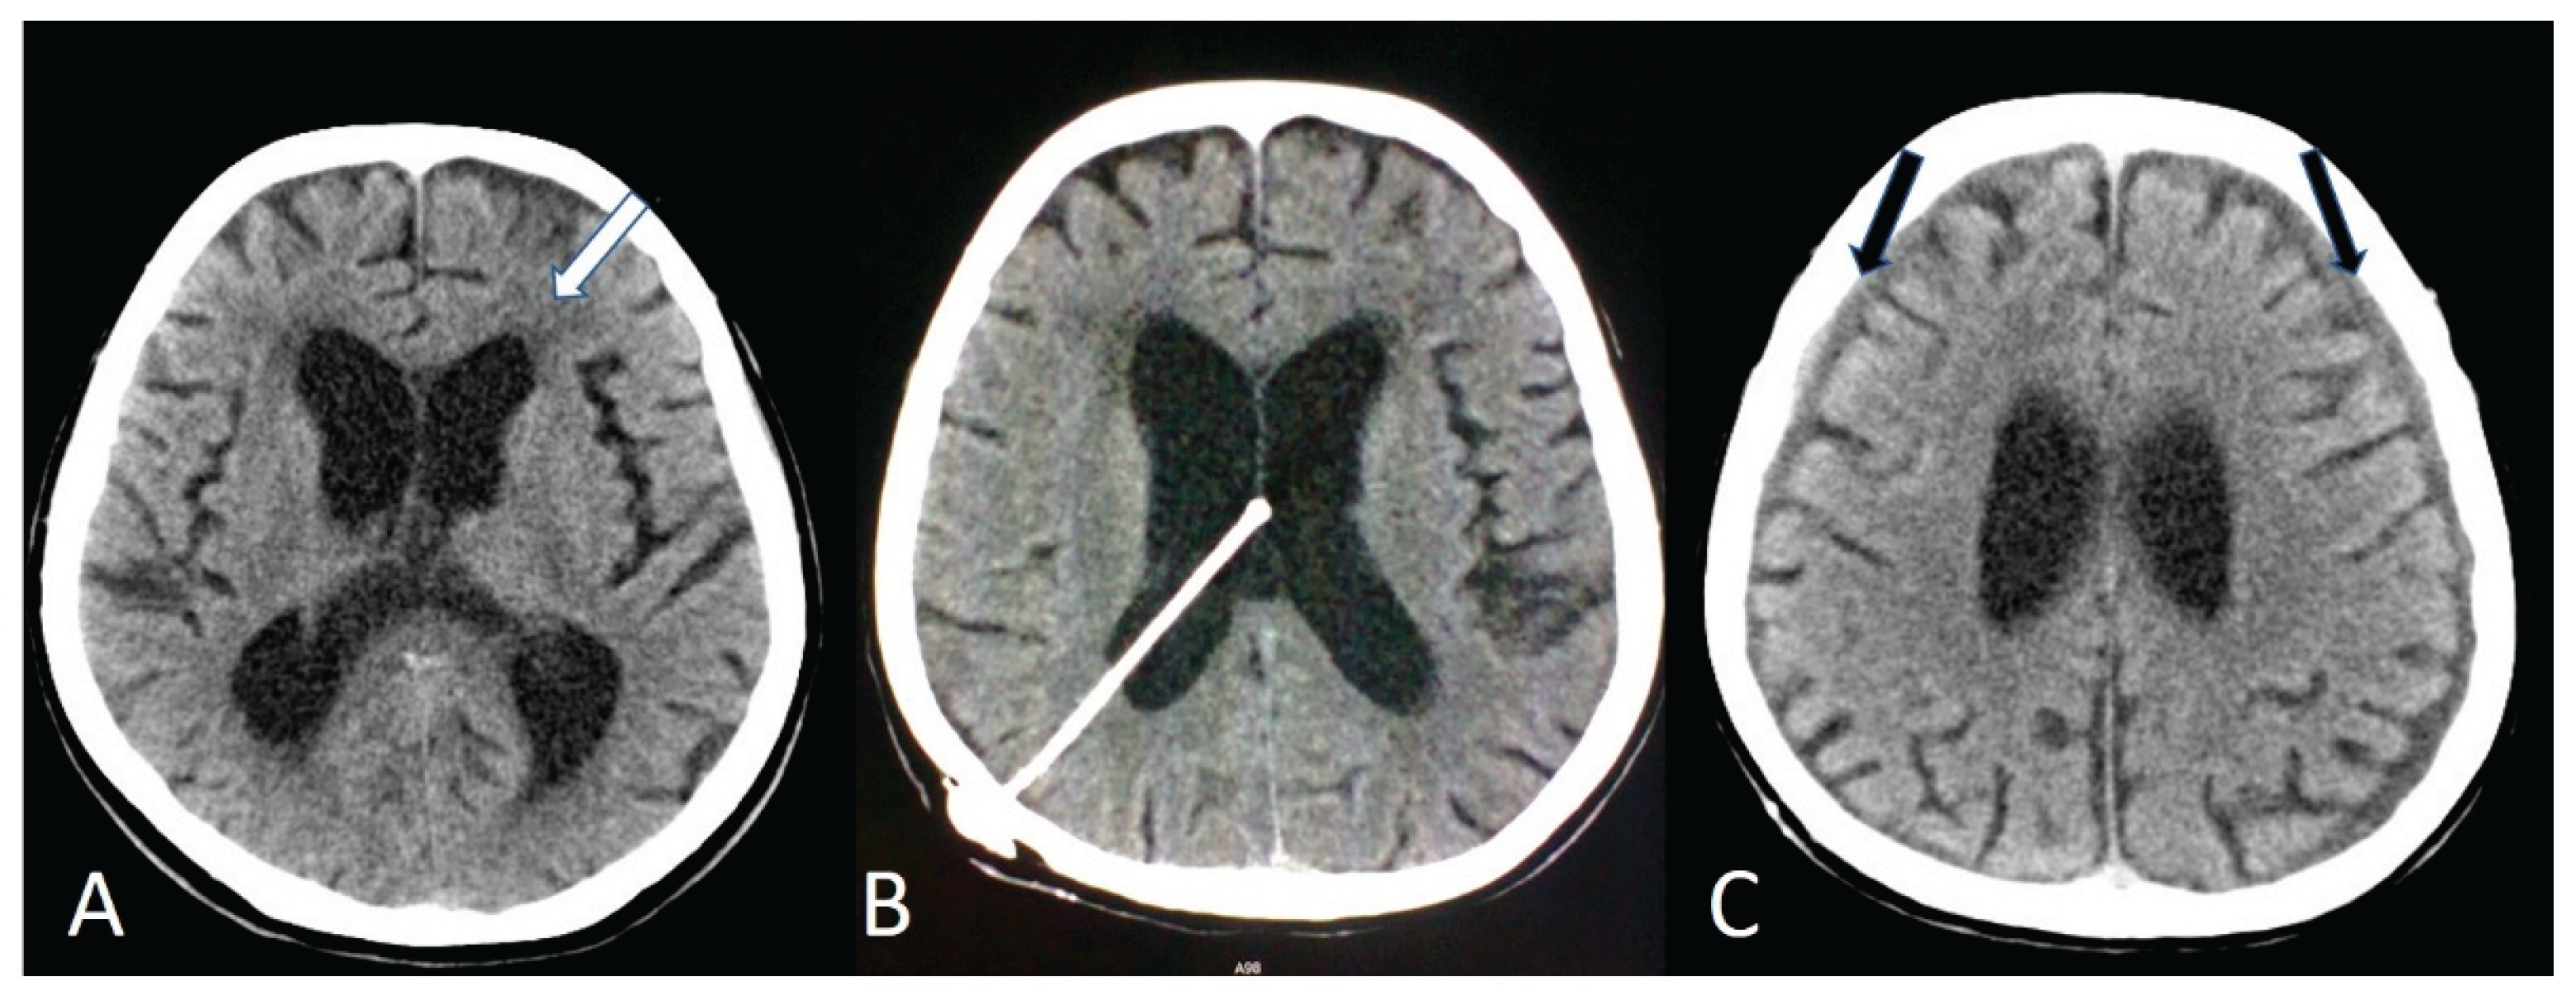

The diagnosis of NPH was based on the clinical presentation and MRI/CT findings. Imaging assessment focused on ventriculomegaly disproportionate to cortical atrophy and enlargement of the lateral ventricles (Figure 1A).

All patients underwent VPS implantation under general anesthesia. A medium-pressure fixed differential valve was used in all cases to ensure procedural standardization. The ventricular catheter was inserted into either the frontal or occipital horn of the lateral ventricle (Figure 1B) based on surgeon preference and patient-specific anatomical considerations. The distal catheter was tunneled subcutaneously and placed into the peritoneal cavity. Standard perioperative antibiotic prophylaxis was administered according to institutional protocol. Postoperative cranial imaging was routinely performed to verify the catheter position and to assess for early complications.

3.4. Complications

Postoperative shunt infections occurred in 2/98 (2.0%) patients. An intracerebral bleeding occurred in 6/98 (6.1%) patients. Revision surgery was required in 14/98 (14.3%) patients and it was most commonly due to overdrainage, which manifested as headache in 9/14 (64.3%) patients, dizziness in 3/14 (21.4%), and bilateral hygromas (Figure 1C) in 5/14 (35.7%). Rare complications following VPS placement included hearing loss, wound dehiscence, and gastrointestinal issues, each occurring in a single patient. A postoperative prophylactic antiepileptic treatment with Levetiracetam was given to 9/98 (9.2%) patients and no seizures were reported in any patient after surgery.

Figure 1. A series of CT scans showing ventricular dilatation and transependymal edema (white arrow) before (A) and after the insertion the VPS (B). Bilateral hygromas (black arrows) indicate an overdrainage condition (C).